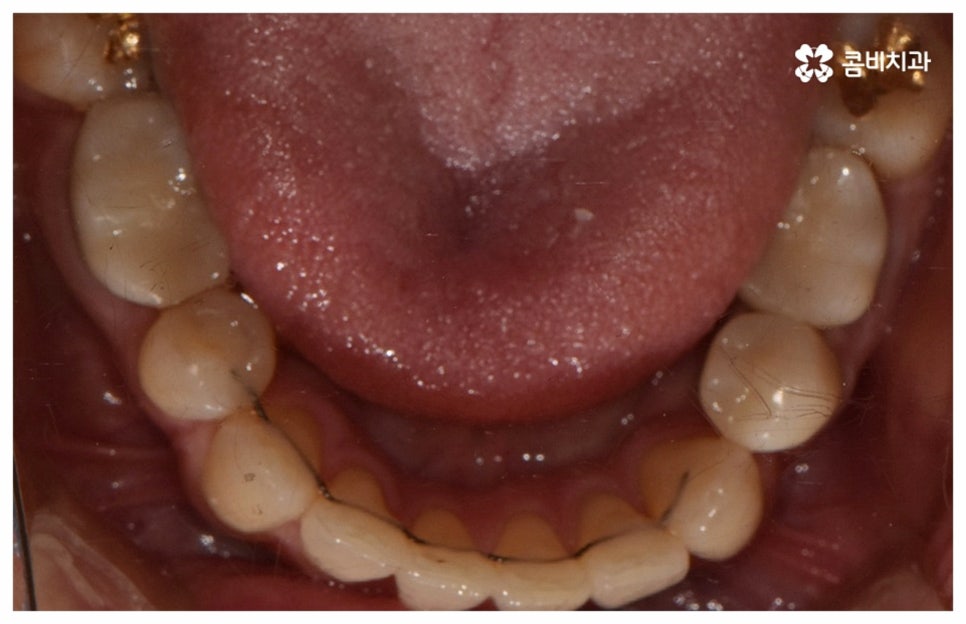

위 사진은 환자분의 동의를 받아 이해를 돕기 위한

사진이며, 실제 치료 결과는 다를 수 있습니다.